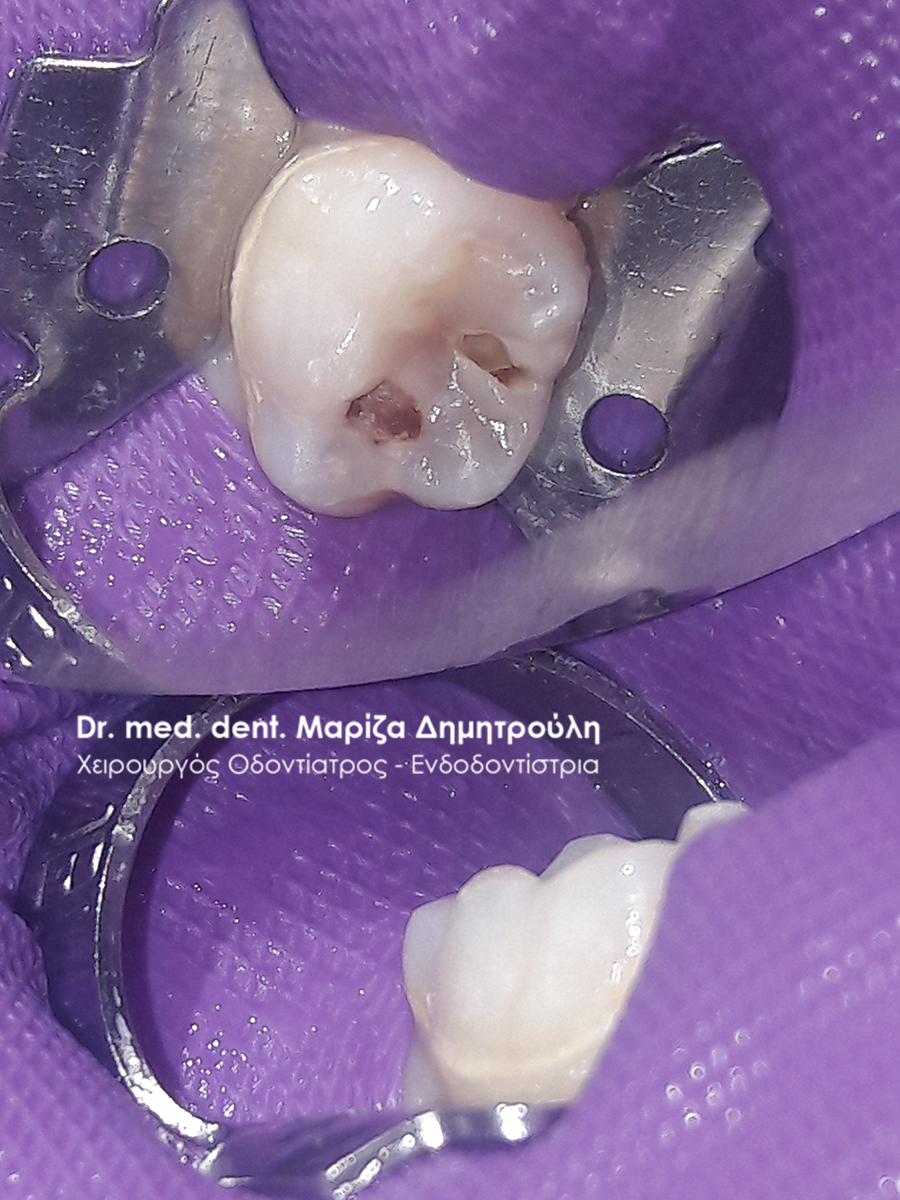

Ο μικρός ασθενής επισκέφτηκε το ιατρείο για την αποκατάσταση του τερηδονισμένου παιδικού δοντιού του. Η ανασύσταση πραγματοποιήθηκε με λευκό σφράγισμα σύνθετης ρητίνης με τη χρήση του απομονωτήρα.

ΠΡΙΝ

Η κοιλότητα του δοντιού καθαρή μετά την αφαίρεση της τερηδόνας

ΜΕΤΑ